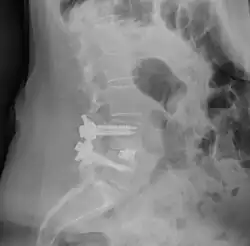

![]() Fusion of L5 and S1 | |